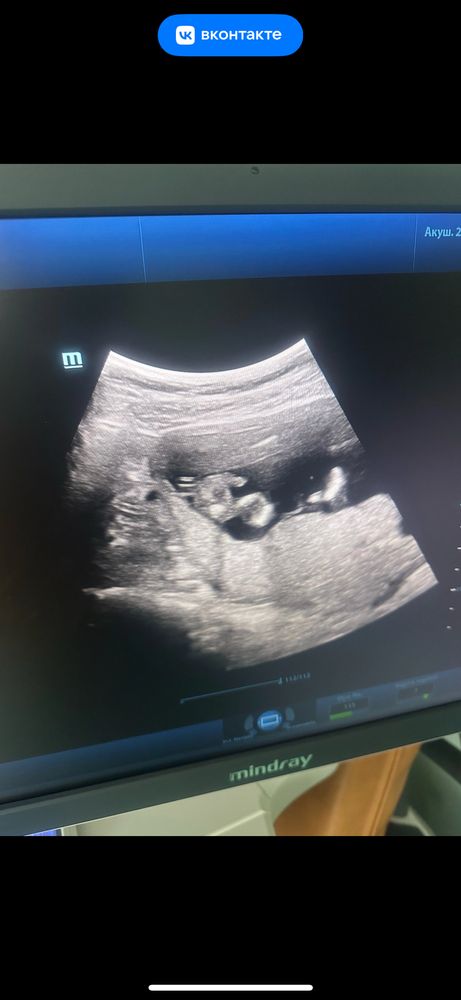

Мне кажется сынок, но я не очень уверена, что смотрю туда. Слева же нога и причинное место

10.07.2024

А что тут вообще на фото? Это какой ракурс?

Best mammy , вроде на попе сидит